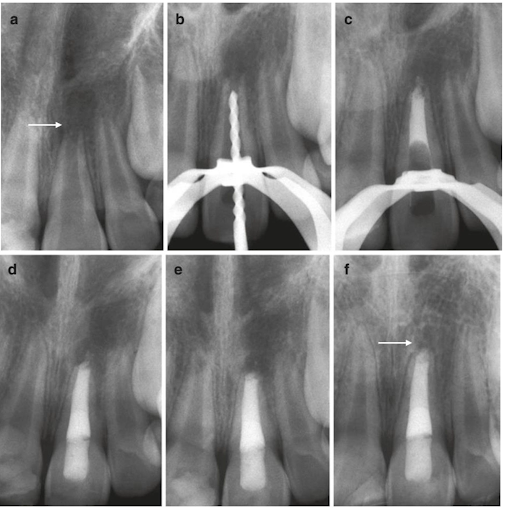

(a) X Quang cận chóp của một răng cửa giữa hàm trên (T) bị chấn thương ở một bệnh nhân nam 8 tuổi cho thấy lỗ chóp mở và vùng thấu quang lớn quanh chóp (mũi tên). (b) Xquang vị trí đặt trâm gần đúng chiều dài làm việc. (c) Xquang kiểm tra vị trí đặt MTA phía chóp. (d) Xquang cuối cùng sau khi trám bít với Gutta percha nóng, lèn chặt và trám. (e) Xquang kiểm tra 3 tháng sau điều trị cho thấy sự lành thương của tổn thương quanh chóp. (f) Xquang kiểm tra 4 năm 6 tháng sau điều trị cho thấy răng đã đóng chóp và lành thương quanh chóp hoàn toàn. Bệnh nhân hiện không có triệu chứng và có đổi màu thân răng.